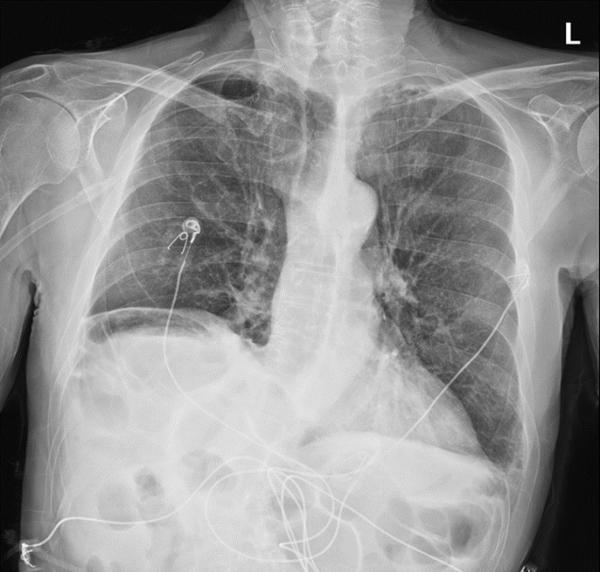

A chest x-ray done prior to intubation showed concern for free air below the right diaphragm (Image 1). A subsequent CT scan showed dense left lower lobe consolidation and confirmed a gaseous collection between the right hemidiaphragm and the liver (Image 2).